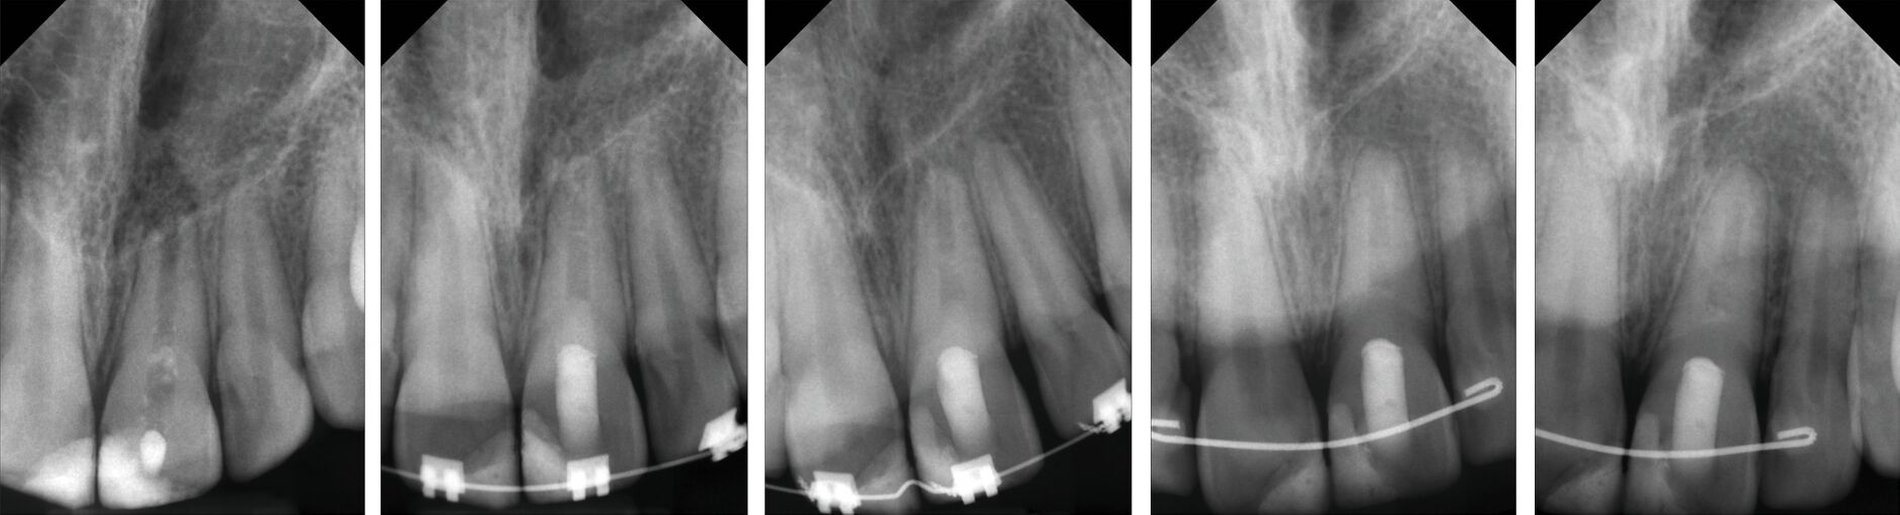

Da der Zahn exakt reponierbar ist, ist bei jugendlichen Zähnen eine Heilung durch Revaskularisation wahrscheinlicher als nach lateraler Dislokation. Dies gilt insbesondere für Zähne, die sich zum Zeitpunkt des Traumas in festsitzender KFO-Behandlung befunden haben (Abbildung 3). Die speziellen mechanischen Verhältnisse können eine Extrusion gleich mehrerer benachbarter Zähne bewirken, wobei in solchen Fällen Komplikationen ausbleiben können, was sich durch eine verstärkte Mundhygiene während der KFO und eine vorbestehende Erweiterung des Foramen apikale durch eine KFO-bedingte Wurzelresorption erklären lässt.

Eine Replantation sollte möglichst rasch erfolgen. Bei sichtbarer Verschmutzung sollte die Wurzeloberfläche schonend gespült werden ohne sie dabei mechanisch zu verletzen (Abbildung 5). Dies kann mit zellphysiologischem Medium der Zahnrettungsbox oder physiologischer Kochsalzlösung erfolgen. Nach der Replantation sollte eine Schienung an beiden Nachbarzähnen für ein bis drei Wochen erfolgen. Bei der Schienenentfernung kann in Abhängigkeit vom klinischen Lockerungsgrad des replantierten Zahnes zunächst nur eine Verbindung zum Nachbarzahn gelöst werden und die Fixation zum zweiten Nachbarzahn um einige Tage verlängert werden.

Nach der Avulsion eines Zahnes ist die Blutversorgung der Pulpa unweigerlich unterbrochen und eine Nekrose insbesondere bei Zähnen mit abgeschlossenem Wurzelwachstum sehr wahrscheinlich. Nach der Replantation des Zahnes besteht demnach das Risiko, dass sich die Pulpa durch ins Wundgebiet verschleppte Bakterien infiziert. Bei Zähnen mit nicht abgeschlossenem Wurzelwachstum ist der erneute Anschluss an die Blutversorgung (Revaskularisation) grundsätzlich möglich und wird mit bis zu 30 Prozent angegeben [Andreasen et al., 1995a; Amaro et al., 2021]. Daher ist die Therapie bei Zähnen mit geschlossenem und mit offenem Apex aus endodontischer Sicht unterschiedlich.

Zähne mit offenem Apex und kurzer Trockenlagerungszeit: Bei replantierten avulsierten Zähnen mit offenem Apex sollte die Einschätzung der Prognose der Desmodontalzellen in derselben Weise wie bei Zähnen mit geschlossenem Apex erfolgen. Entscheidend ist dabei die Lagerung und im ungünstigsten Fall die Dauer der Trockenlagerungszeit des avulsierten Zahnes. Die endodontische Therapie unterscheidet sich jedoch aufgrund der Möglichkeit einer spontanen Revaskularisation und Gewebseinsprossung über den noch offenen Apex bei adäquater extraoraler Lagerung. Daher sollte bei avulsierten Zähnen mit offenem Apex keine unmittelbare Wurzelkanalbehandlung erfolgen, wenn die Trockenlagerungszeit 60 Minuten unterschreitet.

Dennoch kann es notwendig werden, auch bei Zähnen mit offenem Apex endodontische Maßnahmen einzuleiten. Ausschlaggebend ist dabei jedoch nicht die ausbleibende Reaktion auf den Sensibilitätstest, sondern die Entwicklung von Entzündungs- oder Resorptionsprozessen. Es sollte daher ein engmaschiger Recall durchgeführt und bei pathologischen Befunden eine Apexifikation eingeleitet, ein apikaler Verschluss mit hydraulischem Kalziumsilikatzement (Abbildung 5) oder eine Revitalisierung durchgeführt werden [Mente et al., 2013; Mente et al., 2009; Galler et al., 2016; Cvek, 1992].